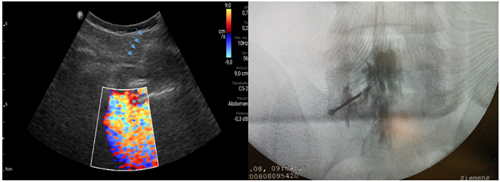

Pacientes y métodos: Un total de 25 pacientes con dolor radicular lumbosacro fueron seleccionados para recibir inyecciones epidurales interlaminares de esteroides en posición decúbito dorsal, utilizando la técnica ecoguiada en plano, en tiempo real, en eje corto o transversal. En todos los casos, un epidurograma de control fue realizado previo a la inyección de la solución de esteroides. El rendimiento de la técnica fue estudiado mediante la tasa de éxito de la misma, entendido como éxito a la obtención de un epidurograma sin necesidad de abandonar la técnica ecográfica en un tiempo menor a 10 minutos. El rendimiento del procedimiento fue estadísticamente evaluado por el método de la suma acumulativa (CUSUM), y la curva de aprendizaje aplicando este método fue construida.

Resultados: La distancia promedio desde la piel al complejo posterior evaluada por el escaneo ecográfico previo al procedimiento fue de 6,7 ± 1,8 cm. De los 25 procedimientos realizados, en 21 se alcanzó el espacio epidural sin ayuda de la fluoroscopia, en un tiempo promedio de 4,8 ± 1,2 minutos. Esto constituye una tasa de éxito del 84 %. En los cuatro procedimientos restantes el espacio epidural fue alcanzado con éxito mediante el uso complementario de la fluoroscopia.

13. Riveros-Perez E, Albo C, Jimenez E, Cheriyan T, Rocuts A. Color your epidural: color flow Doppler to confirm labor epidural needle position. Minerva Anestesiol. 2019;85(4):376-83.

14. Yoon JS, Sim KH, Kim SJ, Kim WS, Koh SB, Kim BJ. The feasibility of color Doppler ultrasonography for caudal epidural steroid injection. Pain. 2005;118(1-2):210-4.